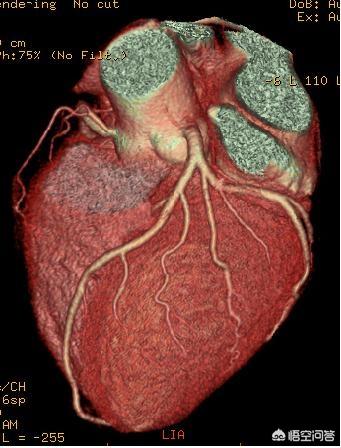

3.冠動脈CTA:腕に留置針を刺して造影剤を押し、肺のCTを撮るように心臓の血管のCTを撮る。内腔狭窄の診断に対する冠動脈CTAの感度と特異度はそれぞれ87.5%と97.2%、陽性適中率と陰性適中率はそれぞれ82.4%と98.1%である。冠動脈CTAは外来で行うことができ、非侵襲的な検査であるため、冠動脈造影を希望しない患者に適している。

冠動脈CT

冠動脈CTは冠動脈が正常かどうかを調べるための補助検査である。まず、撮影システムがスキャンを担当し、スキャンで得られたデータをコンピューターシステムに保存・計算させ、画像を分析・再構成することで、冠動脈血管が医師の目の前で可視化され、病気の診断に役立てることができます。この検査は主に冠状動脈の狭窄の診断の補助に使用され、冠状動脈CTの精度は画像処理ほど良くなく、画像のコンピュータ処理には擬似的な違いがあるかもしれませんが、利点は冠状動脈CTのコストが比較的低く、外傷が少ないことです。